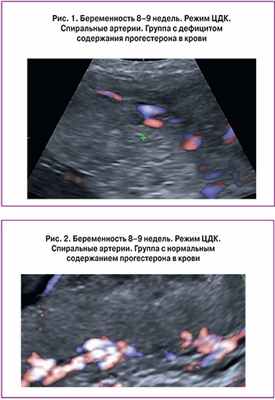

Оценка формирующегося маточно-плацентарного кровотока у пациенток с угрозой прерывания на фоне дефицита прогестерона в I триместре беременности

Цель исследования. Определение зависимости формирования маточно-плацентарного кровотока при угрозе прерывания беременности в I триместре на фоне нормального уровня содержания прогестерона в крови и при гипопрогестеронемии.

Материал и методы. В исследование включена 91 первобеременная пациентка, в сроке гестации 8–12 недель. Пациентки с беременностью, протекающей на фоне угрозы прерывания (n=64) составили I группу, с неосложненным течением беременности (n=27) – II. В обеих группах проведено определение уровня прогестерона в крови. На основании полученных данных I группа была разделена на две подгруппы: IА – c низким уровнем содержания прогестерона в крови (менее 25-го перцентиля) (n=21); IВ – c нормальным уровнем прогестерона (от 25-го до 75-го перцентиля) и повышенным (более 75-го перцентиля) (n=43). С целью оценки маточно-плацентарного кровотока всем пациенткам проводилось трансвагинальное ультразвуковое исследование с допплерографией, трехмерным изображением в реальном времени.

Результаты. На фоне дефицита содержания прогестерона в крови по сравнению с пациентками с нормальным уровнем прогестерона было зафиксировано достоверное повышение показателей кривых кровотока спиральных артерий (р=0,0001) и сосудов желтого тела (р=0,0001), а также снижение объема хориона (р=0,026), индекса васкуляризации хориона (р=0,028) и объема желтого тела (р=0,025). Различий в показателях кривых кровотока маточных артерий и яичниковых артерий по группам не обнаружено.

Заключение. Состояние системы «мать-плацента-плод» определяется параметрами кривых кровотока спиральных артерий и артерий желтого тела, а также объемом хориона, его васкуляризацией, и объемом желтого тела. Нарушение кровотока в спиральных артериях и изменение кровотока в артерии желточного мешка могут рассматриваться как основной допплерометрический признак угрожающего выкидыша и возможных осложнений гестационного процесса в более поздние сроки.